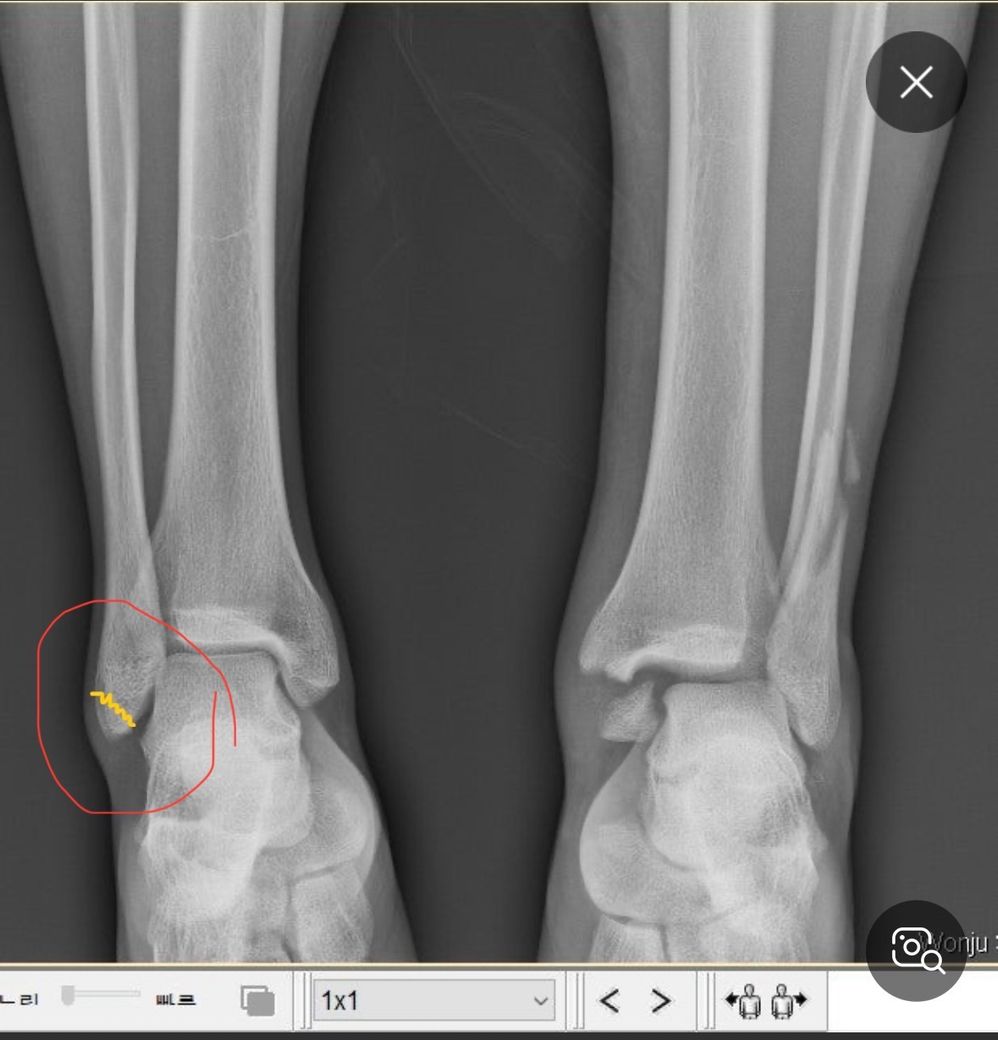

족관절 외과 골절 후유증 남을까요..?

19살인데 넘어지면서 족관절 외관 골절이 됐는데 수술하고 깁스 2주 정도 됐는데 따로 통증은 없습니다. 병원에서는 나이도 어리고 해서 금방 뼈 붙을거고 회복도 빠를거라는데 이거 나중에 후유증 같은거 남을까요..? 예를들어 제대로 못 뛴다거나..그런거

그리고 보통 멀쩡히 거를려면 몇개월정도 필요할까요?

골절은 사진에 노란색으로 표시한 것 처럼 끝부분이 골절 됐습니다

• 1번 째 사진

엑스레이만 봐서는 정확한 상태를 알 수 없습니다. 수술하셨을 때의 진단명 전체와 수술명 정도는 알고 계시거나 병원에 물어보시고 서류로 받으실 수도 있습니다. 단순 외과 골절만 있는지, 외과쪽과 연결되어있는 인대손상이 동반되어있는지 알 수 없기 때문입니다. 가장 정확한건 수술 담당의에게 궁금하신 사항을 모두 물어보시는 것 입니다.